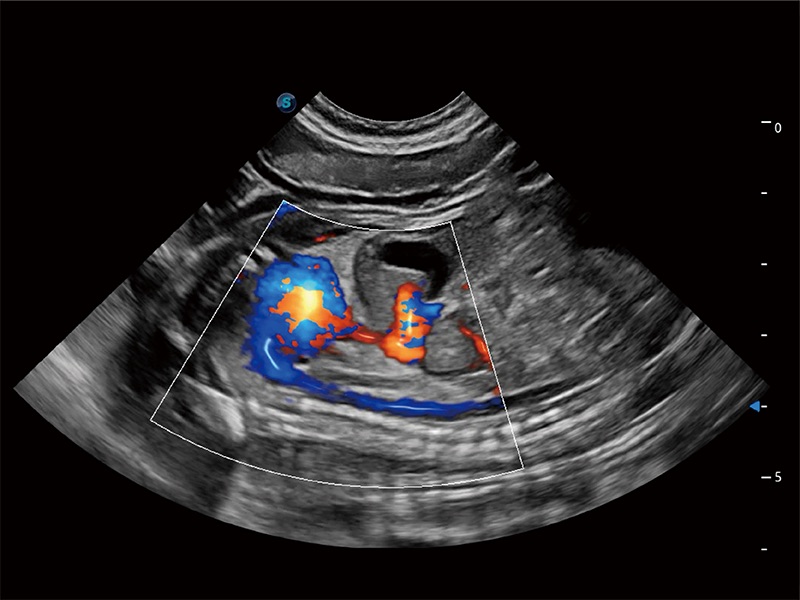

極大提升超低速微細(xì)血流的檢出能力,同時(shí)更精準(zhǔn)地濾除軟組織和超聲信號(hào),為獸用醫(yī)生提供以往無(wú)法通過(guò)常規(guī)血流獲得的疾病診斷信息。

在傳統(tǒng)二維血流成像的基礎(chǔ)上,呈現(xiàn)血流的立體感,具有動(dòng)感的生命力之美。即便是微小的血管也能輕松應(yīng)對(duì),提高了血流的視覺敏感性。